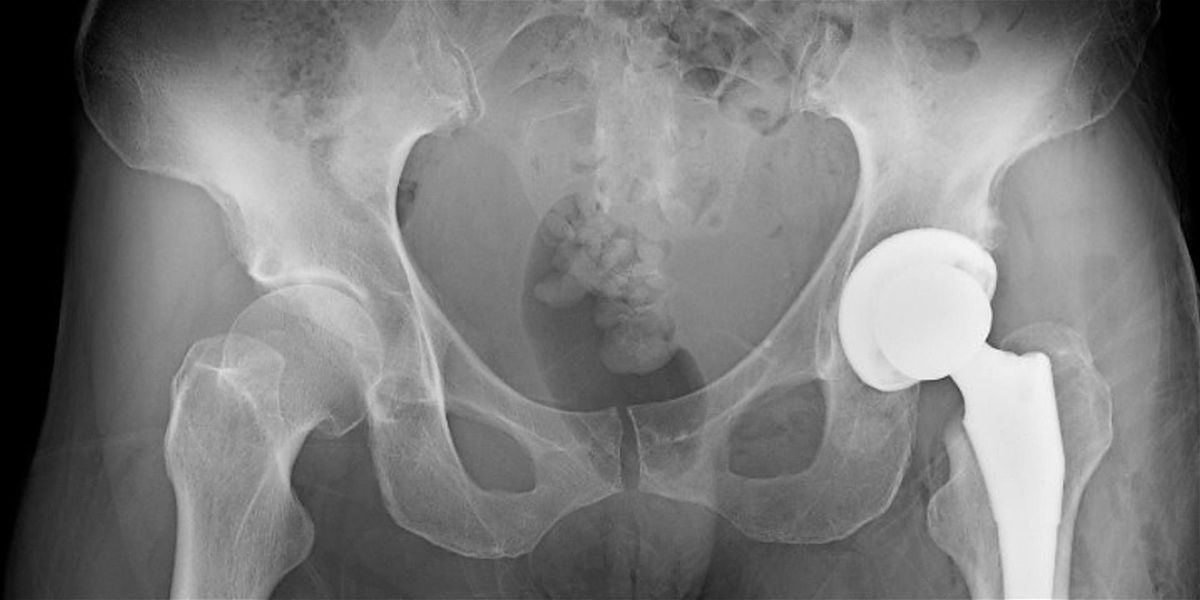

Topic: Total Hip Replacement: Preparation and Return to Dance

Description: Getting a total hip replacement (THR) is a major life decision. Dancers considering and pursuing this procedure often navigate complex emotions as well as logistics. But the recovery process and post-surgery career and life can be rewarding and even transformative.